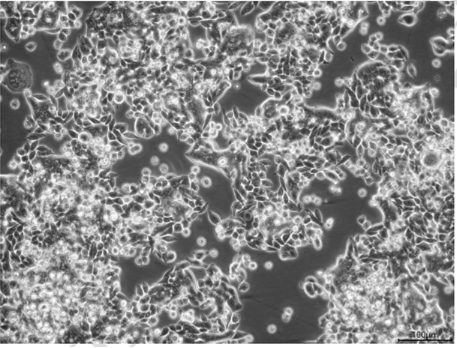

圖片來源于中國科學院典型培養物保藏委員會細胞庫